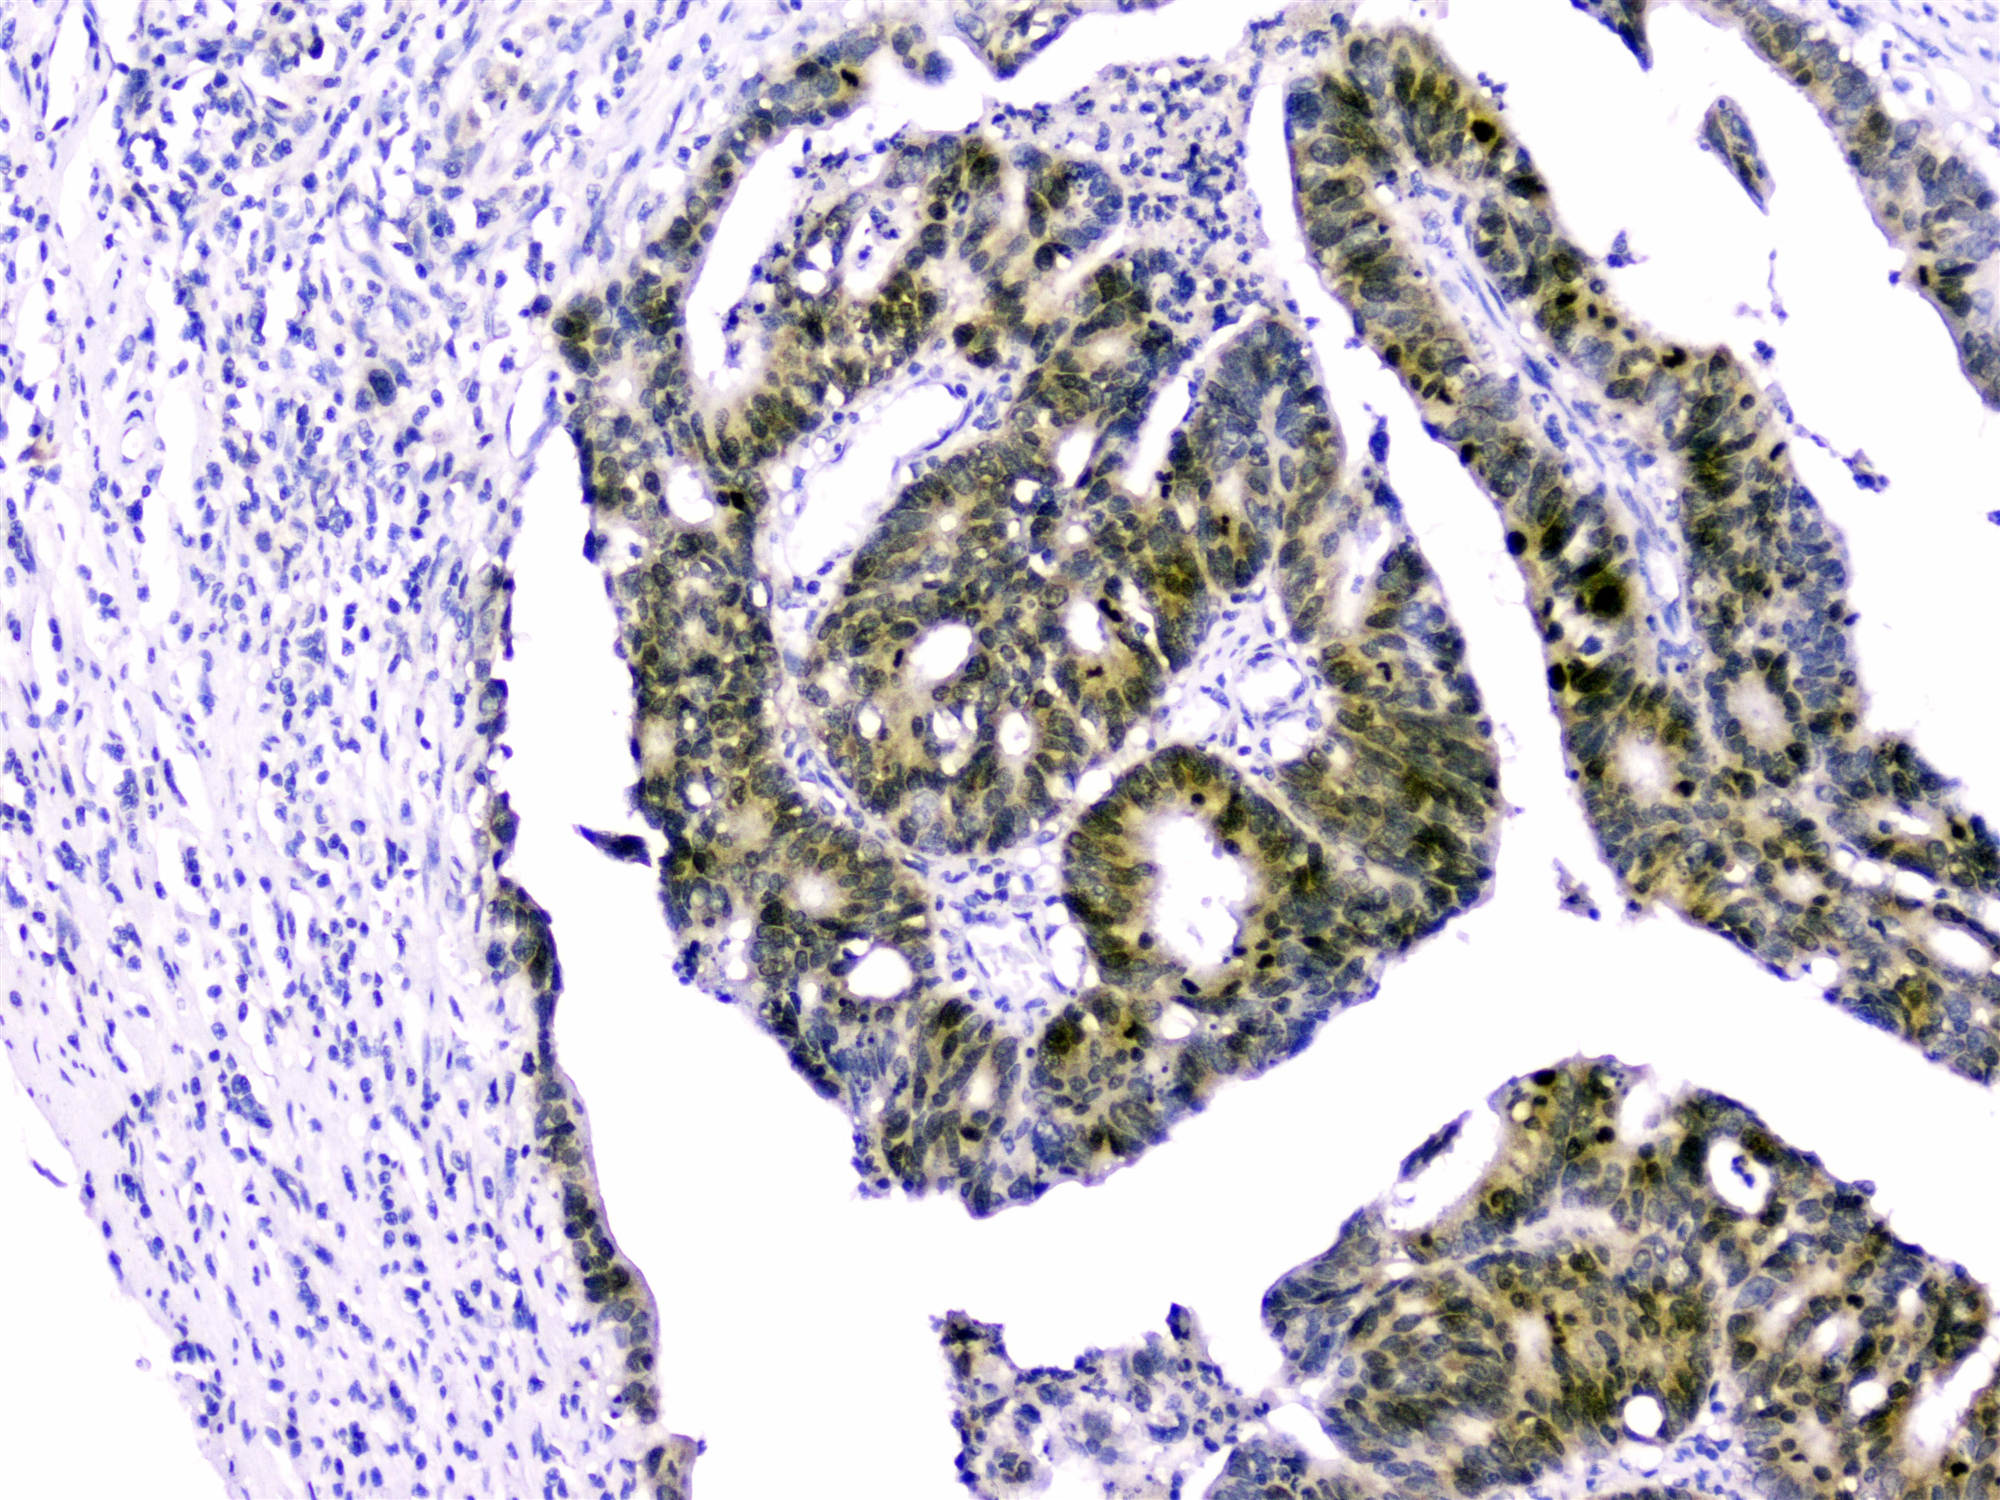

Figure 2. IHC analysis of Survivin using anti-Survivin antibody (A00379).

Survivin was detected in paraffin-embedded section of human intestinal cancer tissues. anti-Survivin Antibody (A00379) overnight at 4°C. Biotinylated goat anti-rabbit IgG was used as secondary antibody The tissue section was developed using Strepavidin-Biotin-Complex (SABC)(Catalog # SA1022) with DAB as the chromogen.